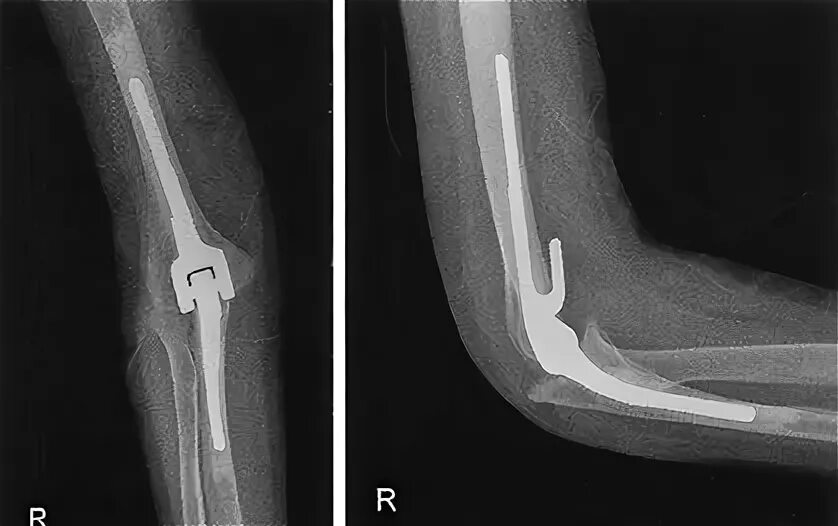

Локтевой сустав инвалидность